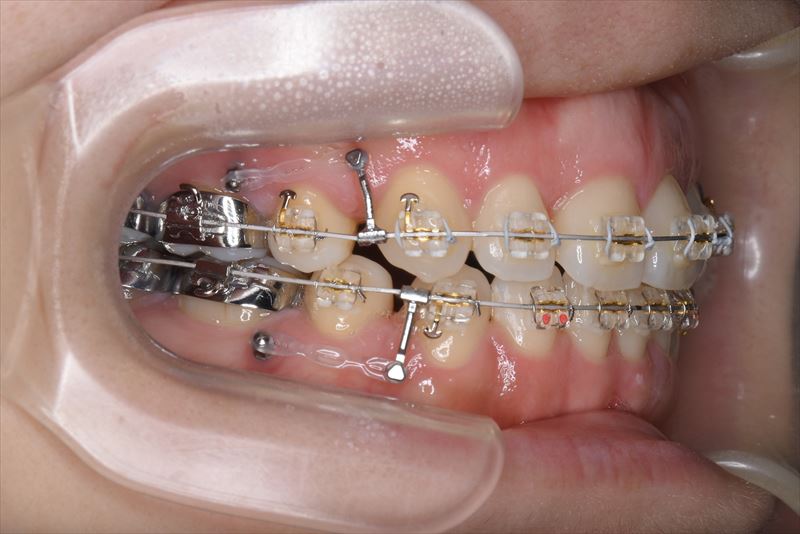

治療中

マルチブラケット装置、アンカースクリュー

上顎両側4番抜歯、下顎両側4番抜歯、下顎両側8番抜歯